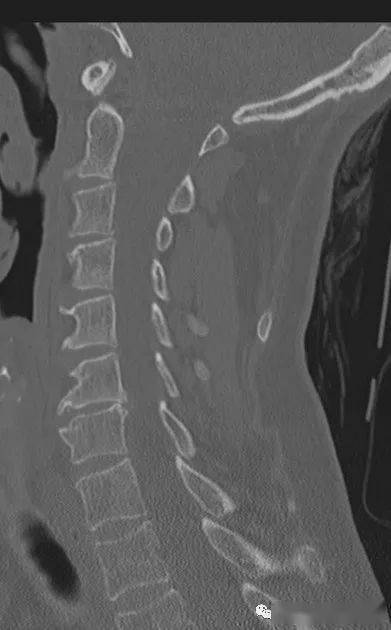

颈椎后纵韧带骨化一例

颈椎后纵韧带钙化典型病例 - 好大夫在线